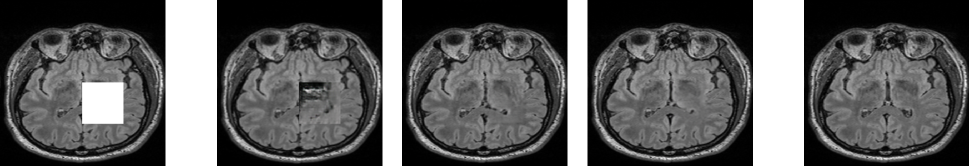

Refer to captionInputCEip-MedGANipA-MedGANTarget

Fig. 3: Qualitative comparison of inpainting for square-shaped regions with ( ) showing the advantages of ipA-MedGAN.

Two distinct set experiments were conducted. The first is the inpainting of traditional square-shaped masks. For this purpose, square-shaped regions of size 64×64646464\times 64 pixels (6.25 % of the total image area) were randomly cropped from the pre-processed scans. The performance of ipA-MedGAN was compared against CE [8] and ip-MedGAN [11], both specifically designed for square-shaped inpainting.

For square-shaped inpainting, the results are presented in Fig. 3 and Table I (a), respectively. CE resulted in the worst inpainting results from a qualitative perspective with the resultant inpainting regions not fitting homogeneously into the surrounding context information. The ip-MedGAN framework enhanced the inpainting quality both qualitatively and quantitatively. However, as illustrated by ( ) in Fig. 3, minor visual artifacts can still be depicted at the boundary of the inpainted regions. Additionally, the exact location of the region of interest must be supplied as input to ip-MedGAN during training. The proposed ipA-MedGAN overcomes both of the previous drawbacks by eliminating the boundary artifacts with no required prior localization of the masked regions.